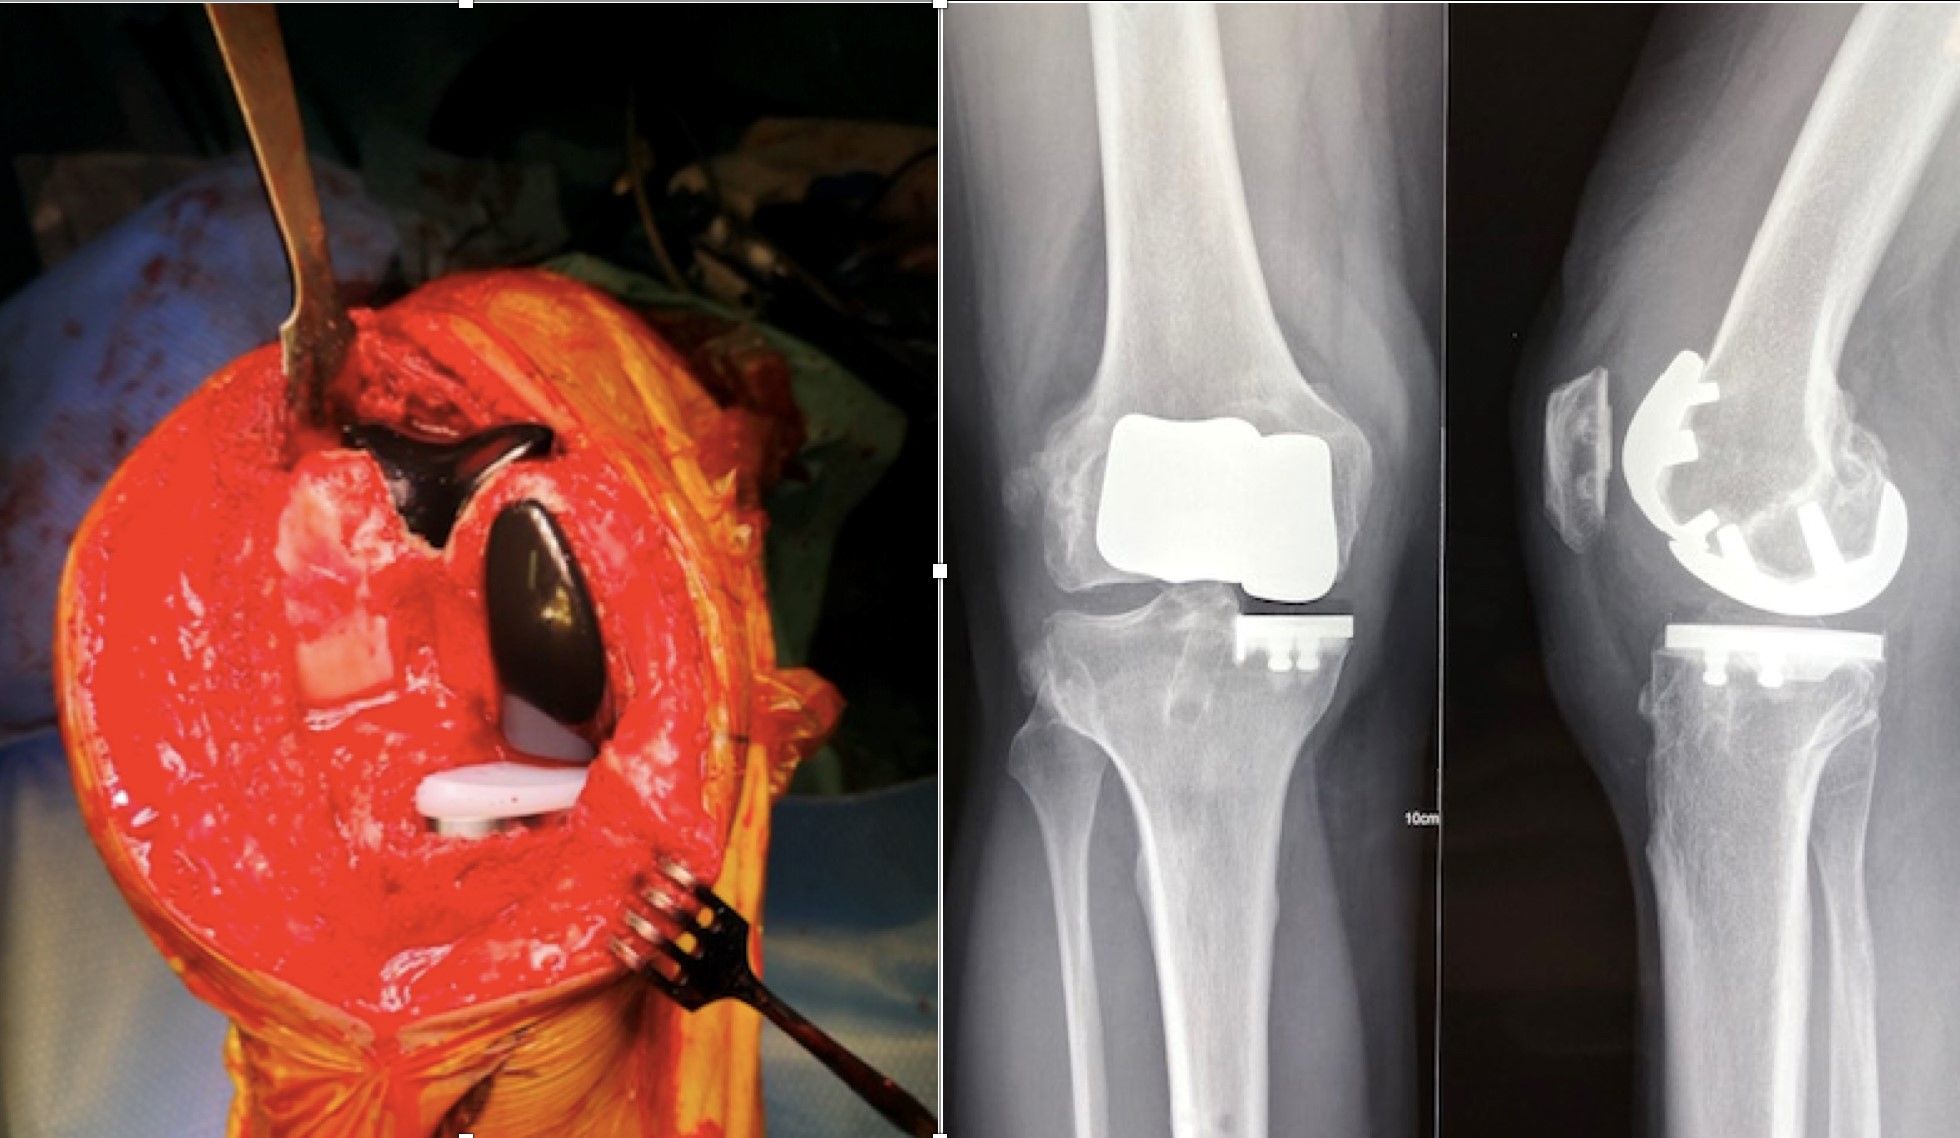

a. Bicruciate-retaining arthroplasty

There is a long history of bicruciate-retaining total knee replacements (Fig. 22) with promising long-term results but a reputation as a technically demanding procedure. Robotics have provided considerable assistance for surgeons undertaking this type of arthroplasty, which requires a meticulous understanding of the difference in joint space between the lateral and medial compartments, as well as highly accurate bone preparation (Fig. 23). Protecting the tibial spines is also much easier when using a bur guided by a robotic handpiece.